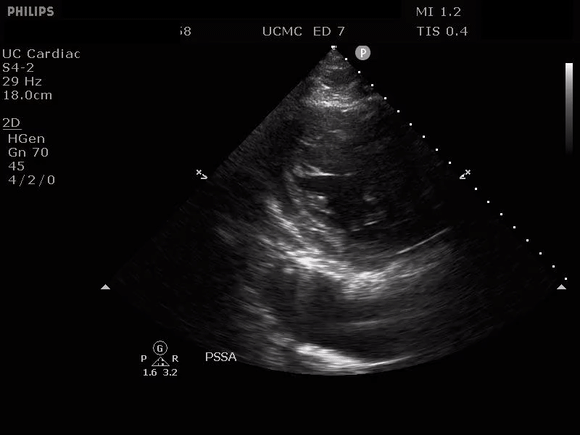

Parasternal long axis view with dissection flap visible in the proximal ascending aorta

The parasternal short axis view demonstrates evidence of a mobile hyperechoic structure within an anechoic tubular structure deep to the heart, which represents a dissection flap within the descending aorta. The parasternal long view demonstrates a dilated proximal aorta with a dissection flap originating at the aortic root. Aortic dissection is a challenging diagnosis to make, and the remainder of this article will discuss the bedside evaluation for aortic dissection with point of care ultrasound.